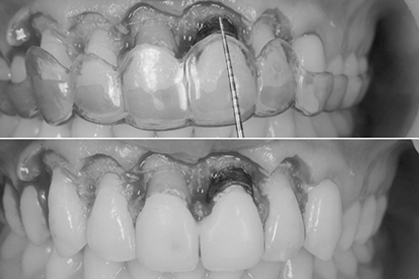

初診時

初診時、前歯の角度はかなり前に向かって生えています。この状態から神経の治療を行うことなく、かぶせ物で角度を変えるのは、限界があるとお伝えして、神経の治療をまず行なってから、歯を削って仮歯を入れる治療計画を伝えて行なった。

セラミックセット時

初めに仮歯に置き換えてから問題なければ、仮歯を最終的な形のプロビに置き換えます。プロビにて歯肉とのマッチングや形や出具合を確認してもらい約1ヶ月の期間使用してもらいます。問題がなければ、最終的な型採りを行い、セラミックの試適、そして完成となりました。